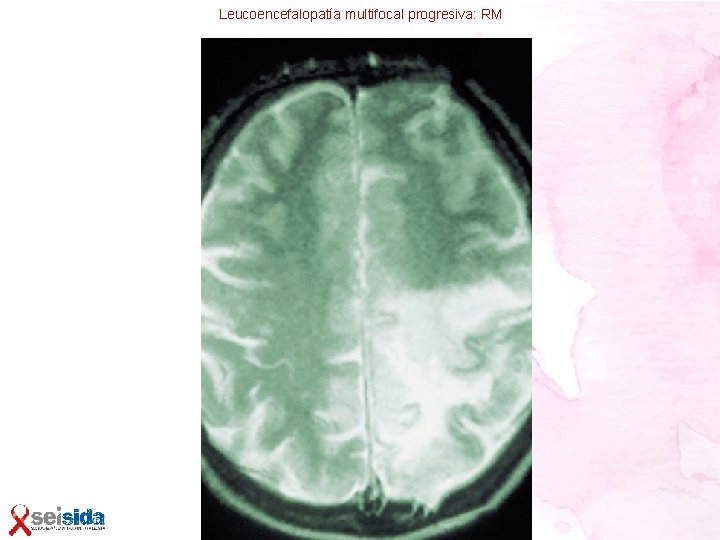

Leucoencefalopatía multifocal progresiva • Ocurre en la enfermedad por VIH muy avanzada Etiología: virus JC • Produce una enfermedad desmielinizante, con lesiones confluyentes en sustancia blanca subcortical • Histología: edema de oligodendrocitos, con inclusiones intranucleares que son las partículas del virus JC Clínica • Déficits focales de curso subagudo, en principio sin alteración del nivel de conciencia Diagnóstico: • Por los síntomas, asociado a hallazgos radiológicos en RMN cerebral: lesiones en sustancia blanca, hiperintensas en T 2, y tras haber descartado otras etiologías • Estudio por PCR en LCR. Resultados poco sensibles Tratamiento • No existe un tratamiento eficaz, la mejor opción es iniciar u optimizar el TAR con pautas potentes y con buena penetración en SNC

Leucoencefalopatía multifocal progresiva: RM